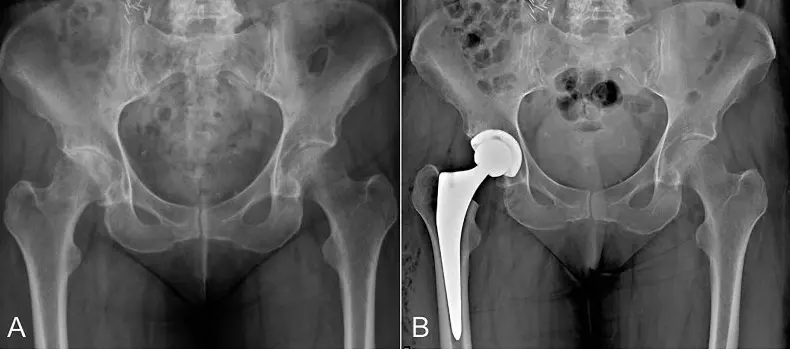

Hip replacement (also called total hip arthroplasty) is a surgical procedure that replaces a damaged or worn‑out hip joint with a prosthetic implant. Candidates typically suffer from severe osteoarthritis, rheumatoid arthritis, avascular necrosis or hip fractures that don’t respond to conservative treatments. Signs you may need hip replacement include:

During your consultation, your surgeon will review your imaging and medical history to determine the best approach and implant type for your anatomy and lifestyle.